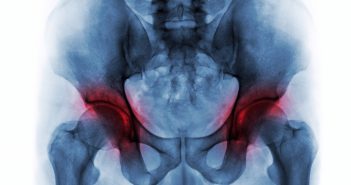

Purinarme Ernährung

„Gicht ist eine typische Wohlstanderkrankung, die sich hervorragend durch eine Ernährungsumstellung behandeln lässt“, sagt Oecotrophologin…